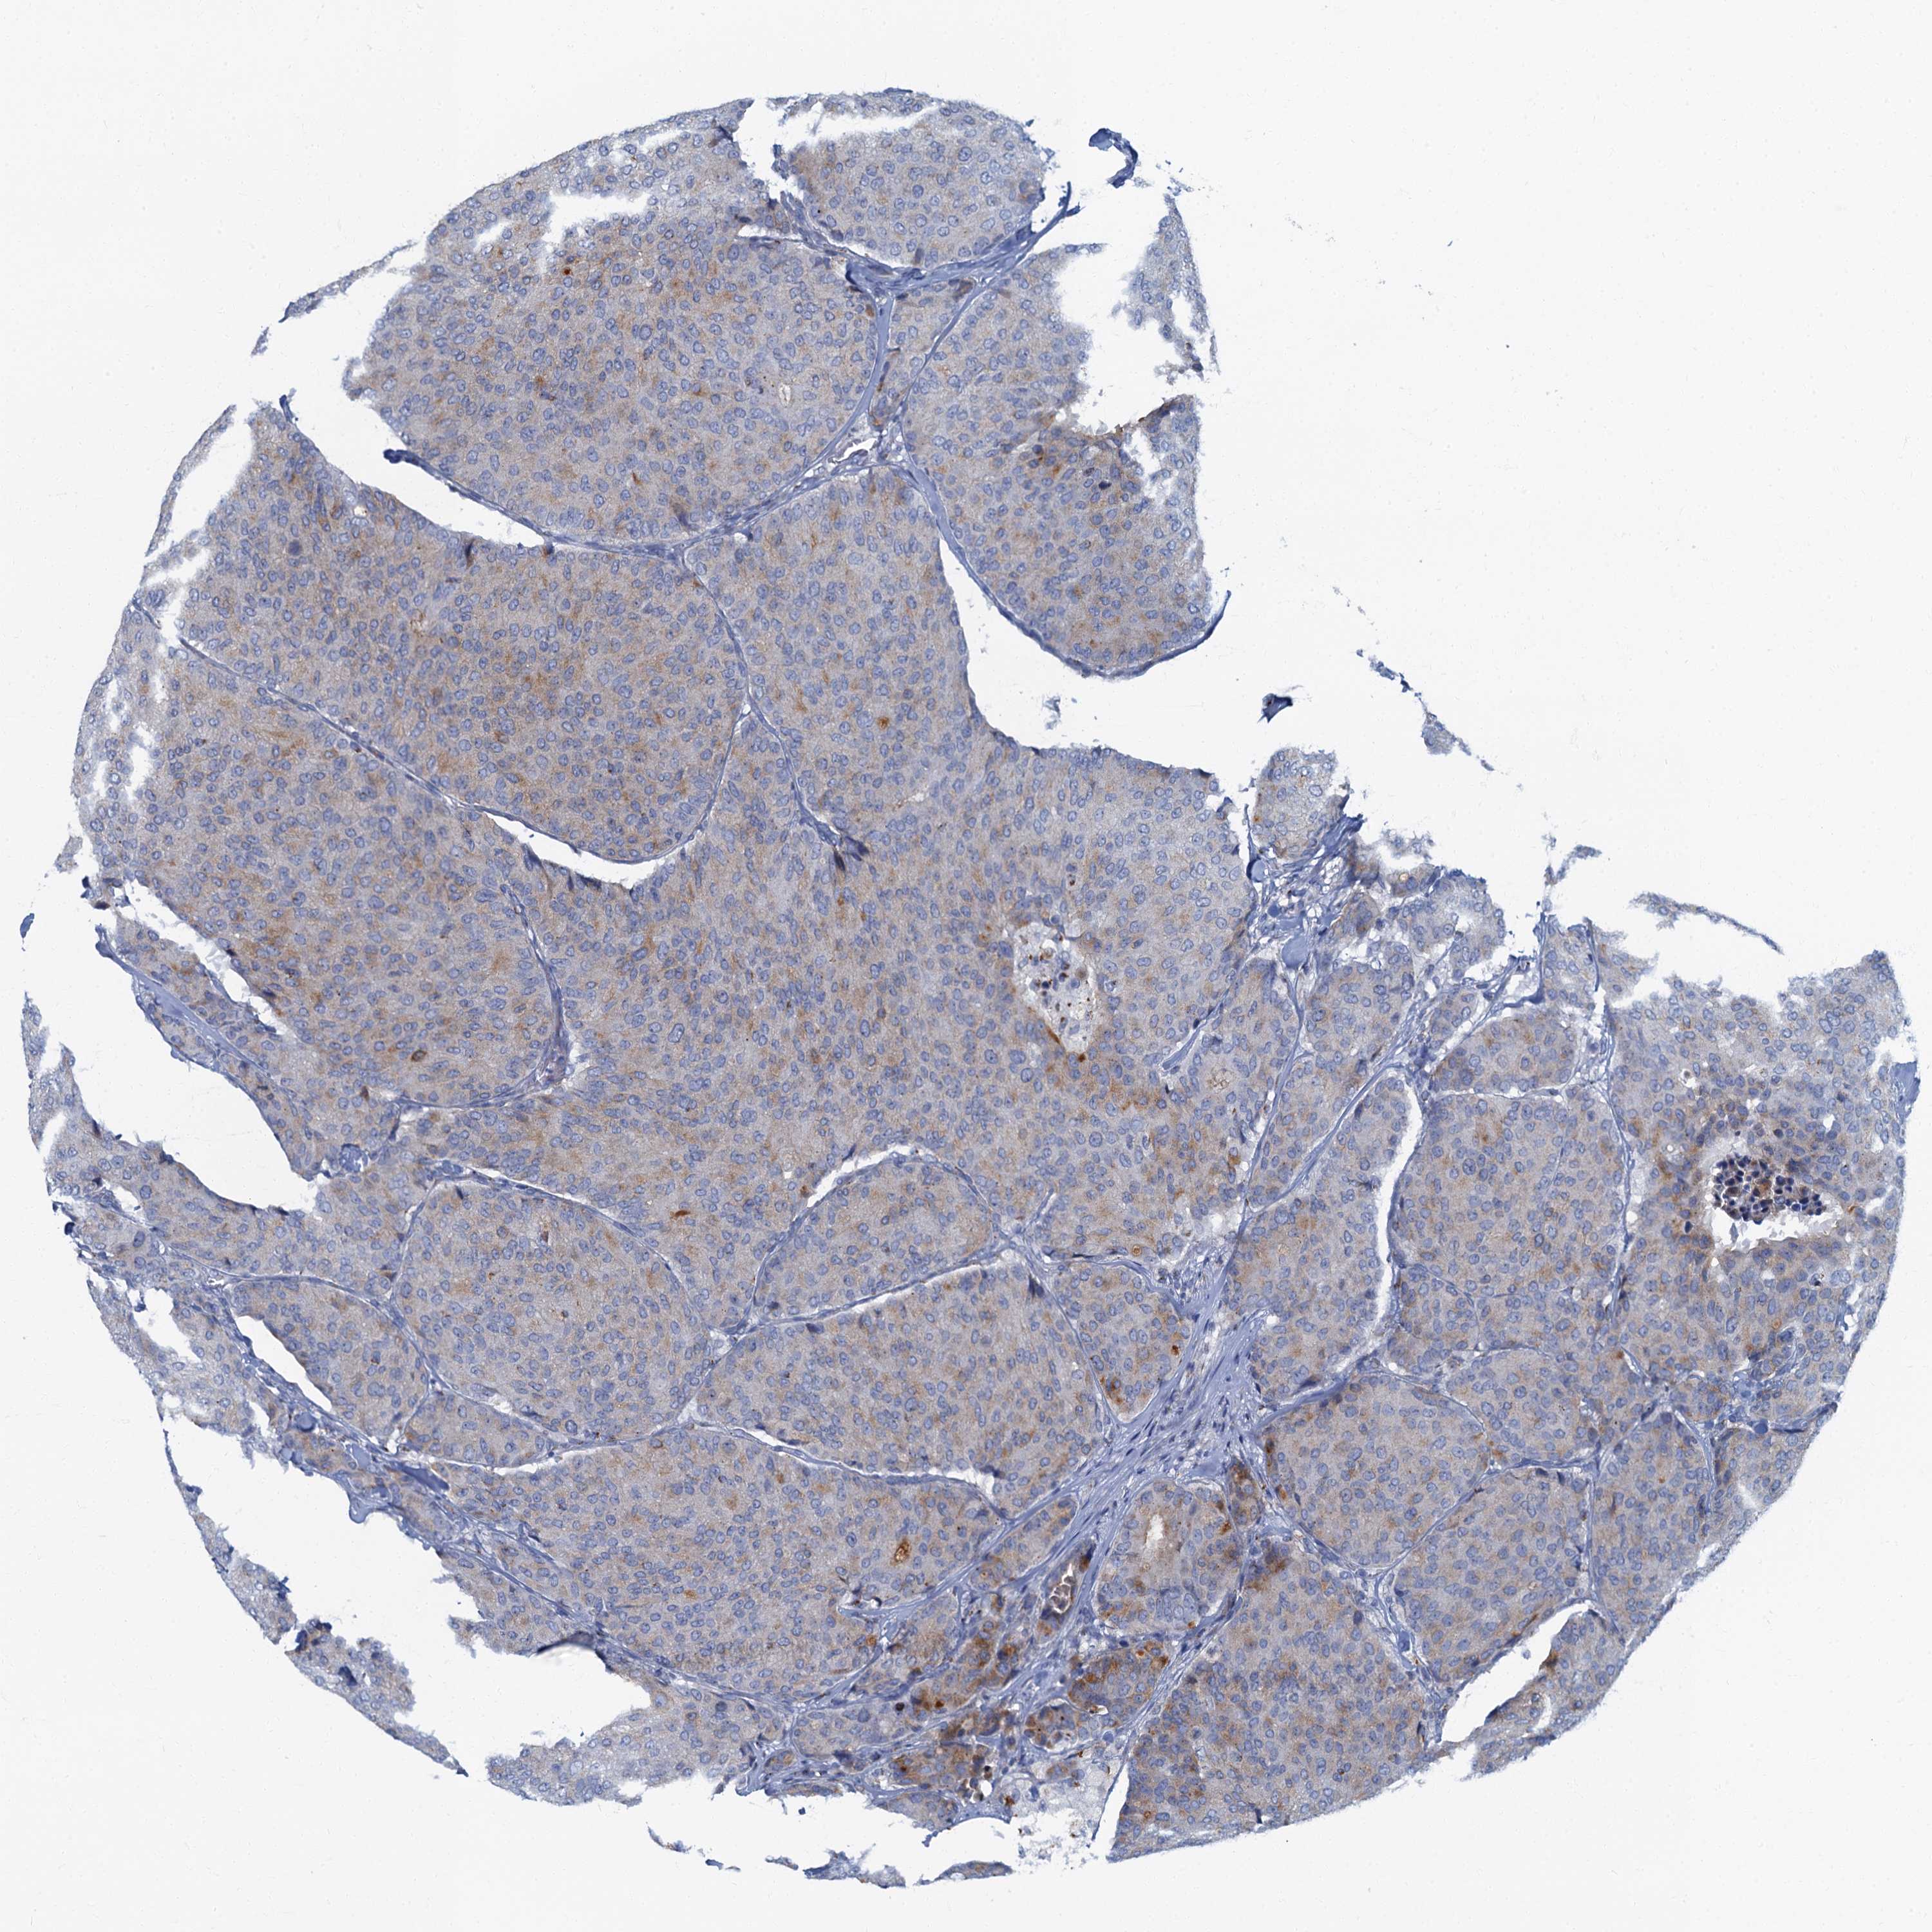

BRCA TCGA BRCA VALIDATION PROTEIN EXPRESSION